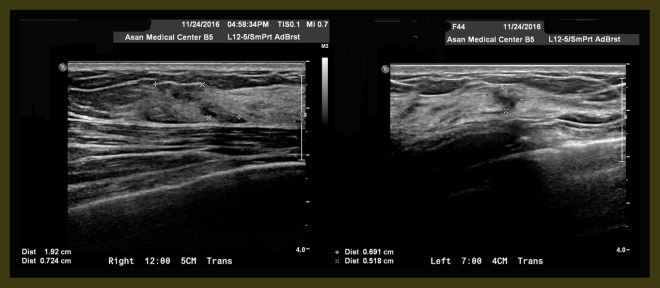

수술 전의 초음파 자료에 양측에 각기 1.92×0.7cm(right breast 12시 방향 5cm 거리)와 0.69×0.51cm(left breast 7시 방향 4cm 거리)의 두개의 크지 않은 종양이 보였다.

0-2.jpg